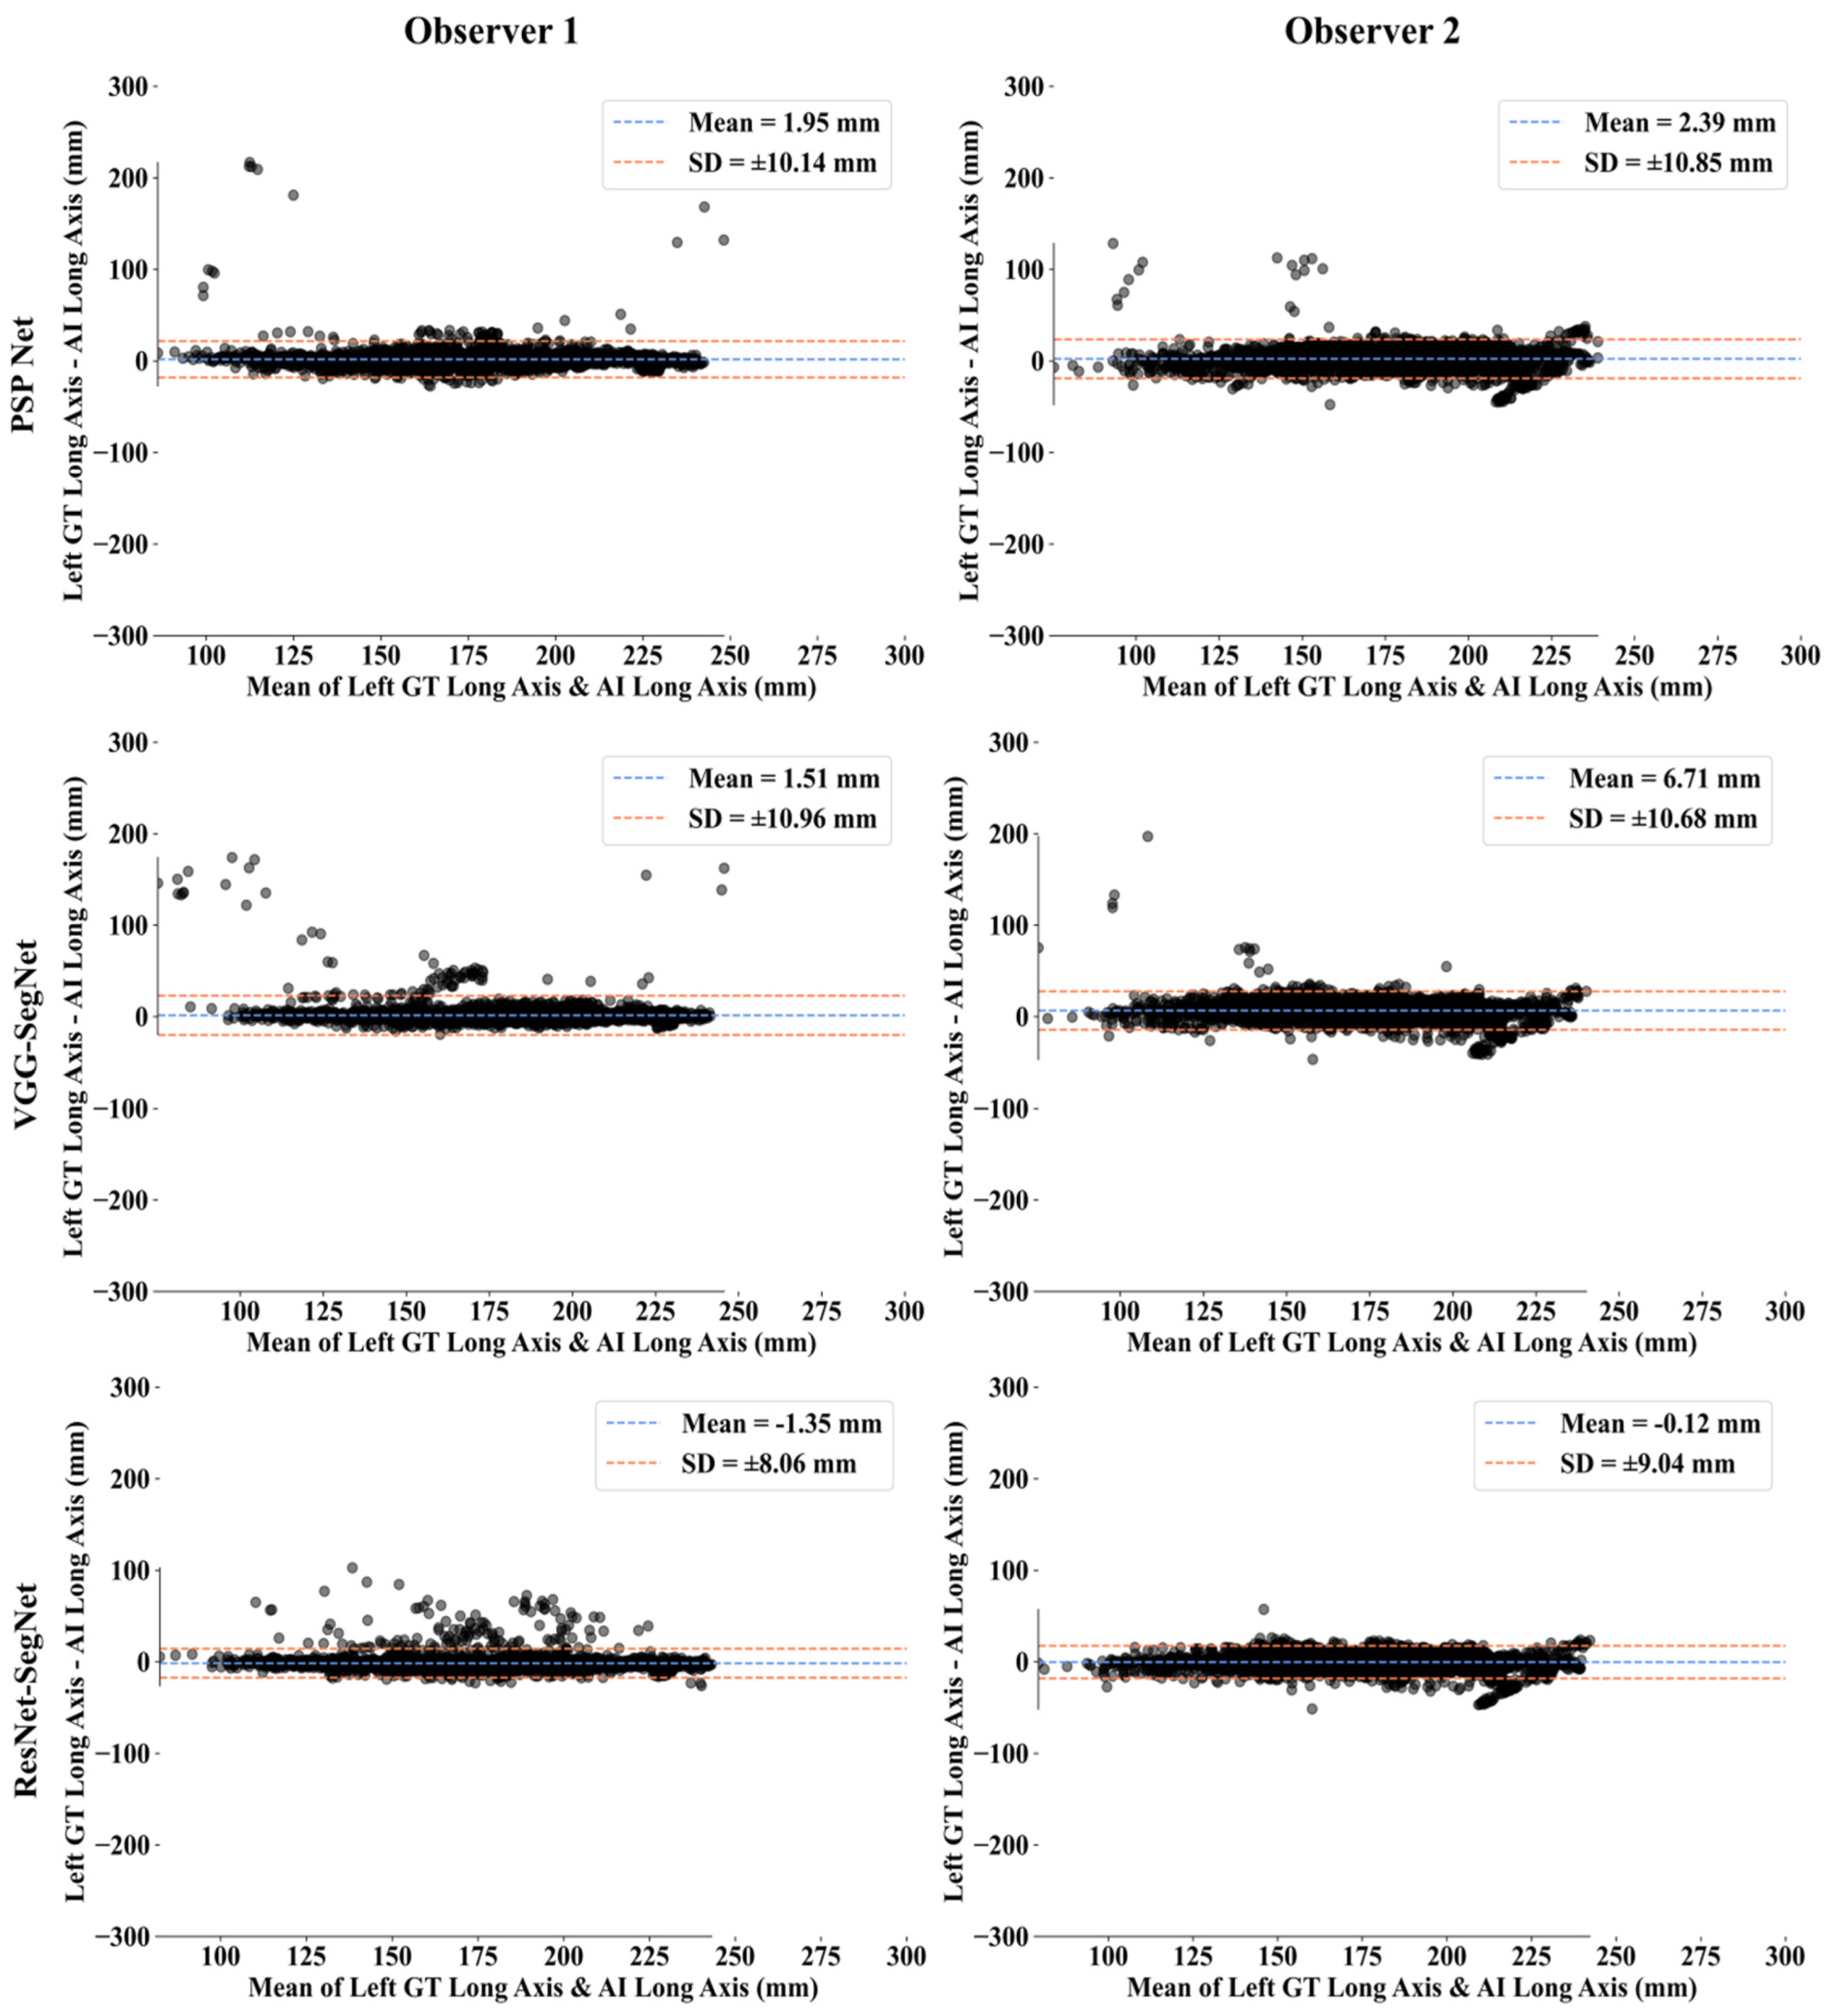

Bland-Altman Plots for Lung Long Axis Error

Statistical Tests